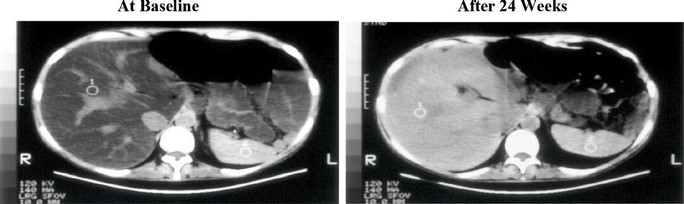

Figure 8. Liver CT Images: Before and After Treatment with IV Choline Chloride

GRAPHIC

Alkaline Phosphatase:

At baseline, LS mean ALP concentration was 239.3 ± 118.93 in the IV Choline Chloride group and 148.1 ± 100.2 in the placebo group. The MMRM analyses demonstrated statistically significant decreases in ALP concentrations at Week 12 (p = 0.008), Week 16 (p = 0.005), Week 20 (p = 0.007), and Week 24 (p = 0.005) for the IV Choline Chloride group, demonstrating a reduction in cholestasis. A trend towards significance was observed at Week 4 (p = 0.076) and Week 6 (p = 0.056). At Week 34, 10 weeks after discontinuation of IV Choline Chloride treatment, LS mean change from baseline in ALP concentrations still demonstrated statistically significant decreases (p = 0.002), demonstrating a significant improvement in cholestasis with treatment with IV Choline Chloride (Figure 9).